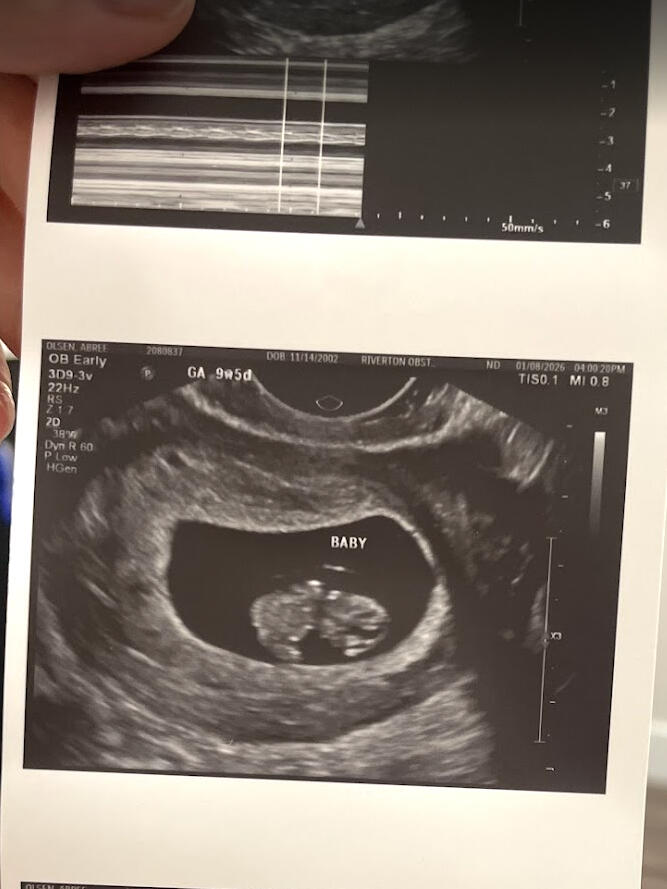

Ultra sound @ March 25th

It has only been three months and three weeks since we found out we are having a child.Since then, we have gained a bassinet in our bedroom and a closet filled with new baby clothing. New artwork for our nursery and overall has been the subject of conversation every single day since.It is sufficient to say that our lives have changed forever.Having this drastic a change in such a short time has come with much stress and complications, and almost all aspects of our lives.Most surprising are the emotional changes we have undergone over the past three months. As it turns out, (from parenting books and colleagues’) husbands and wives will go through drastic hormonal changes while the wife is pregnant.All this has led to a lot of planning for our future baby. There are times when I feel more stress than I've ever felt in my entire life.However, in the same breath, I believe I have also felt the most gratitude and love for my family that I have ever felt.For sure, things are differentBut overall, despite all the sleepless nights and worrying about our baby’s future, I’ve been able to see the world in a different, more positive light than ever before.Abree and I have been dreaming of this moment and have been planning for our new child. Now that it is here, it feels almost surrealWe are very excited